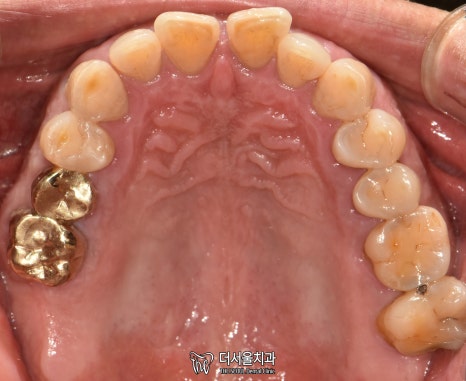

5. 완료

현충일 공휴일 정상진료

최종 완료된 모습입니다.

첫 진료 때보다 깔끔해졌죠?

치아와 비슷한 색으로 된

‘지르코니아’ 크라운을 씌워드렸는데요.

튼튼하다는 특징도 있어

많은 분께 선호되고 있는 재료입니다.

실제로 보면 이렇게

다른 치아와 크게 다르다는 점이 없죠?

환자분도 치료 결과에 만족스러워 하셨습니다.

엑스레이로 한번 더 체크했을 때도

뼈와 잘 붙었습니다.